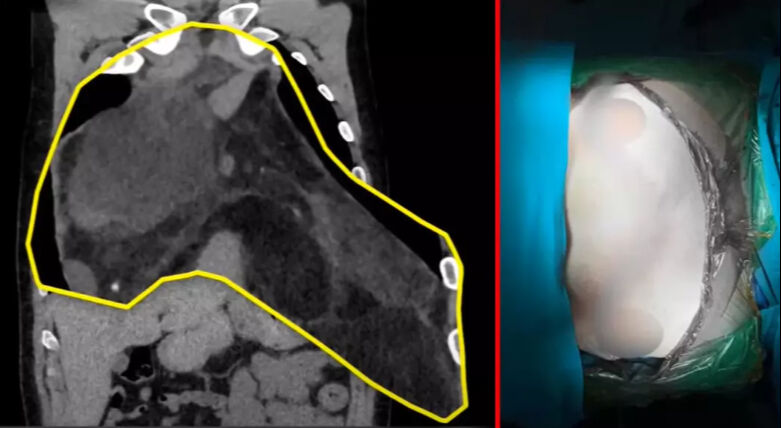

"Çap olarak 47 santim boyunda ve 4 kilo ağırlığında bu çapta Türkiye'de bilinen ve bildirilen en büyük vaka. Artı dünyada da sayılı 1-2 vakadan birisi. Hastalığı aslında bir göğüs akciğer boşluğundaki bir kitleydi. Oldukça hızlı büyüyen ve göğsünün içinde çok ciddi yer kaplayan bir tümördü.

Yandan yapılan torukotomi dediğimiz kesiyle de yapma imkanımız yoktu. Çünkü bu kitle akciğerin sağından başlıyor, kalbi eziyor ve oradan da sol akciğerin tamamını dolduruyordu. Yani göğüs kafesini sağdan sola açıp bu iman tahtası dediğimiz sternum kemiğinde keserek göğsü kaldırarak yapıyoruz. Sonucumuz başarılı oldu."

Özgürel’de hastalığının ne denli büyük olduğunu operasyondan çıkınca öğrendi. Özgürel ameliyat sonrası yaptığı açıklamada "Ben onu 26 santim biliyordum. Çıktığında öğrendim 47 santim olduğunu. Bütün PET çekiminde, MR'larda falan hep 26 santimlik bir kitle var diye söyleniyordu. Şok geçirdim. İçimden bir yaratık çıkmış resmen." ifadelerini kullandı.